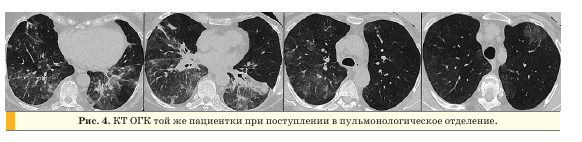

При обследовании в пульмонологическом отделении на КТ ОГК в нижних и средних отделах легких с обеих сторон сохранялись участки по типу “матового стекла” (объем измененной паренхимы остался прежним), утолщение междольковых и внутридольковых перегородок, внутригрудные лимфоузлы были увеличены до 8 мм, подмышечные лимфоузлы не увеличены (рис. 4).